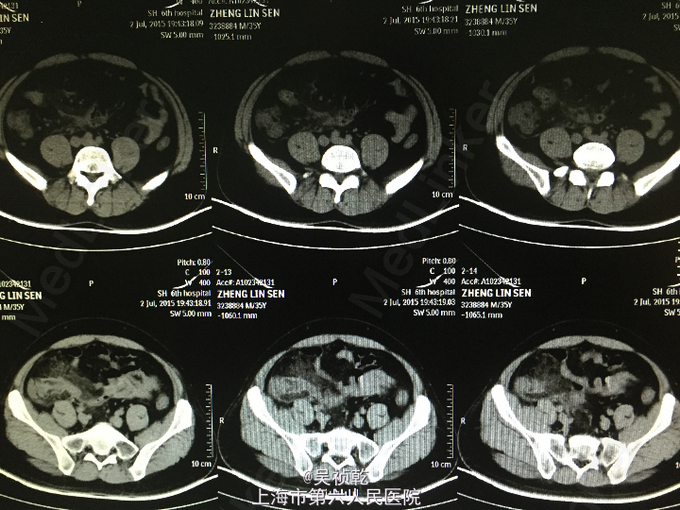

患者男性,35岁。因“右下腹疼痛1天,伴恶心、呕吐”入院。患者1个月前无明显诱因下脐周疼痛,后转移至右下腹,疼痛固定。无恶心呕吐,无头晕乏力。于外院拟尿路感染治疗,补液消炎1周后症状缓解。昨日下午,右下腹疼痛加剧,伴发热,体温约38.2摄氏度,有恶心,呕吐症状。故来我院治疗,完善各项检查,查腹部CT;阑尾形态增粗伴阑尾壁肿胀,回盲部及阑尾周围可见大量渗出,前列腺密度均匀,未见明显增大,两侧精囊未见明显异常,膀胱充盈可,盆腔未见明显肿大淋巴结,盆腔未见明显积液,。为进一步治疗收住入院。患者自起病以来,精神可,胃纳差,大便如常,小便如常,体重未见明显下降,睡眠一般。

查体:腹部平坦,无胃肠型。腹壁柔软,有压痛,位于右下腹,伴反跳痛,无腹部包块,振水音阴性,未触及肝;未触及脾 ,无移动性浊音,肝区无叩痛。肠鸣音正常。结肠充气试验:阴性;腰大肌试验:阴性;闭孔内肌试验:阴性。 辅查:2015-7-3 生化检验报告:血清钠(干式) 136 mmol/L ↓,总蛋白(干式) 60 g/L ↓,白蛋白(干式) 32 g/L ↓,谷草转氨酶(干式) 14 U/L ↓,总胆红素(干式) 62 μmol/L ↑。 血常规检验报告:白细胞 14.3 X10^9/L ↑,红细胞 5.18 X10^12/L ,淋巴细胞百分比 9.5 % ↓,嗜酸性细胞百分比 0.1 % ↓,中性细胞百分比 84.8 % ↑,嗜酸性细胞绝对值 0.01 X10^9L ↓,单核细胞绝对值 0.8 X10^9L ↑,中性细胞绝对值 12.1 X10^9L 腹部CT:阑尾形态增粗伴阑尾壁肿胀,回盲部及阑尾周围可见大量渗出,前列腺密度均匀,未见明显增大,两侧精囊未见明显异常,膀胱充盈可,盆腔未见明显肿大淋巴结,盆腔未见明显积液,。